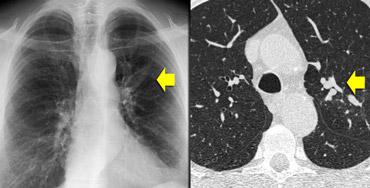

Ca lâm sàng minh họa: Ung thư lan tràn theo đường bạch huyết

Hình ảnh

Dày vách khu trú, không đều ở thùy trên phổi phải trên bệnh nhân có tiền sử ác tính đã biết. Dấu hiệu này điển hình cho ung thư phổi lan tràn theo đường bạch huyết.

Các đặc điểm hỗ trợ chẩn đoán bao gồm:

- Hạch bạch huyết trung thất

- Tổn thương dạng nốt ở phổi trái, nhiều khả năng là di căn.

Ung thư phổi lan tràn theo đường bạch huyết (PLC):

- Trong 50% trường hợp, dày vách có tính chất khu trú hoặc một bên, giúp phân biệt với các nguyên nhân khác (ví dụ: sarcoidosis, phù phổi do tim).

- Hạch bạch huyết rốn phổi có thể thấy trong 50% bệnh nhân, và thường có tiền sử bệnh ác tính.